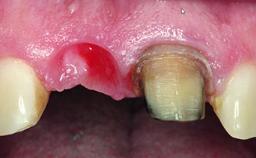

A 30-year-old patient presented at our clinic with a chief complaint of pain in her endodontically treated right maxillary central incisor (tooth 11) with a post-and-core and a fixed single crown. She had a very high lip line, a medium to thin soft-tissue phenotype, and a medium scalloped gingival contour. She also had high esthetic expectations because of her young age and beautiful smile. However, her expectations were realistic and she understood the risks of the treatment. At the initial clinical examination there was a slight mobility of tooth 11; no fistula was observed. The patient also had a single crown on the adjacent tooth 21. Both restorations were old and esthetically deficient. A digital periapical radiograph showed a very small periapical radiolucency, a thick intraradicular post, and no separation between root fragments.

Bone Augmentation Staged

Soft Tissue Grafting Simultaneous